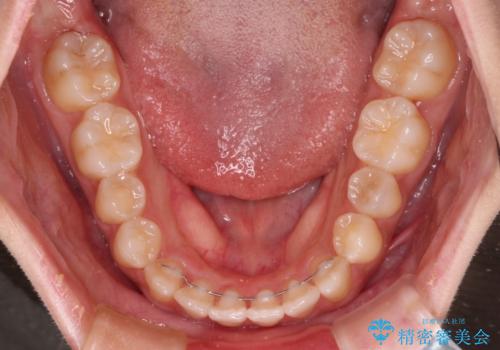

- 上下のデコボコと奥歯の咬みにくさを気にして来院された患者様です。

上顎骨の幅が下顎骨よりも小さく受け口傾向であったため、拡大装置により上顎骨の骨幅を広げて上下関係を改善し、その後インビザラインにて歯並びを整えることとしました。

下顎歯列は上顎歯列内に収まるように並んでいますが、上顎骨の幅が狭いと、下顎臼歯が全体的に舌側に傾斜した歯列となってしまいます。

舌側に傾斜した歯列は奥歯に力の負担がかかりやすく、歯磨きがしにくいなどの問題があるため、上顎骨拡大により舌側傾斜を改善することが可能となります。